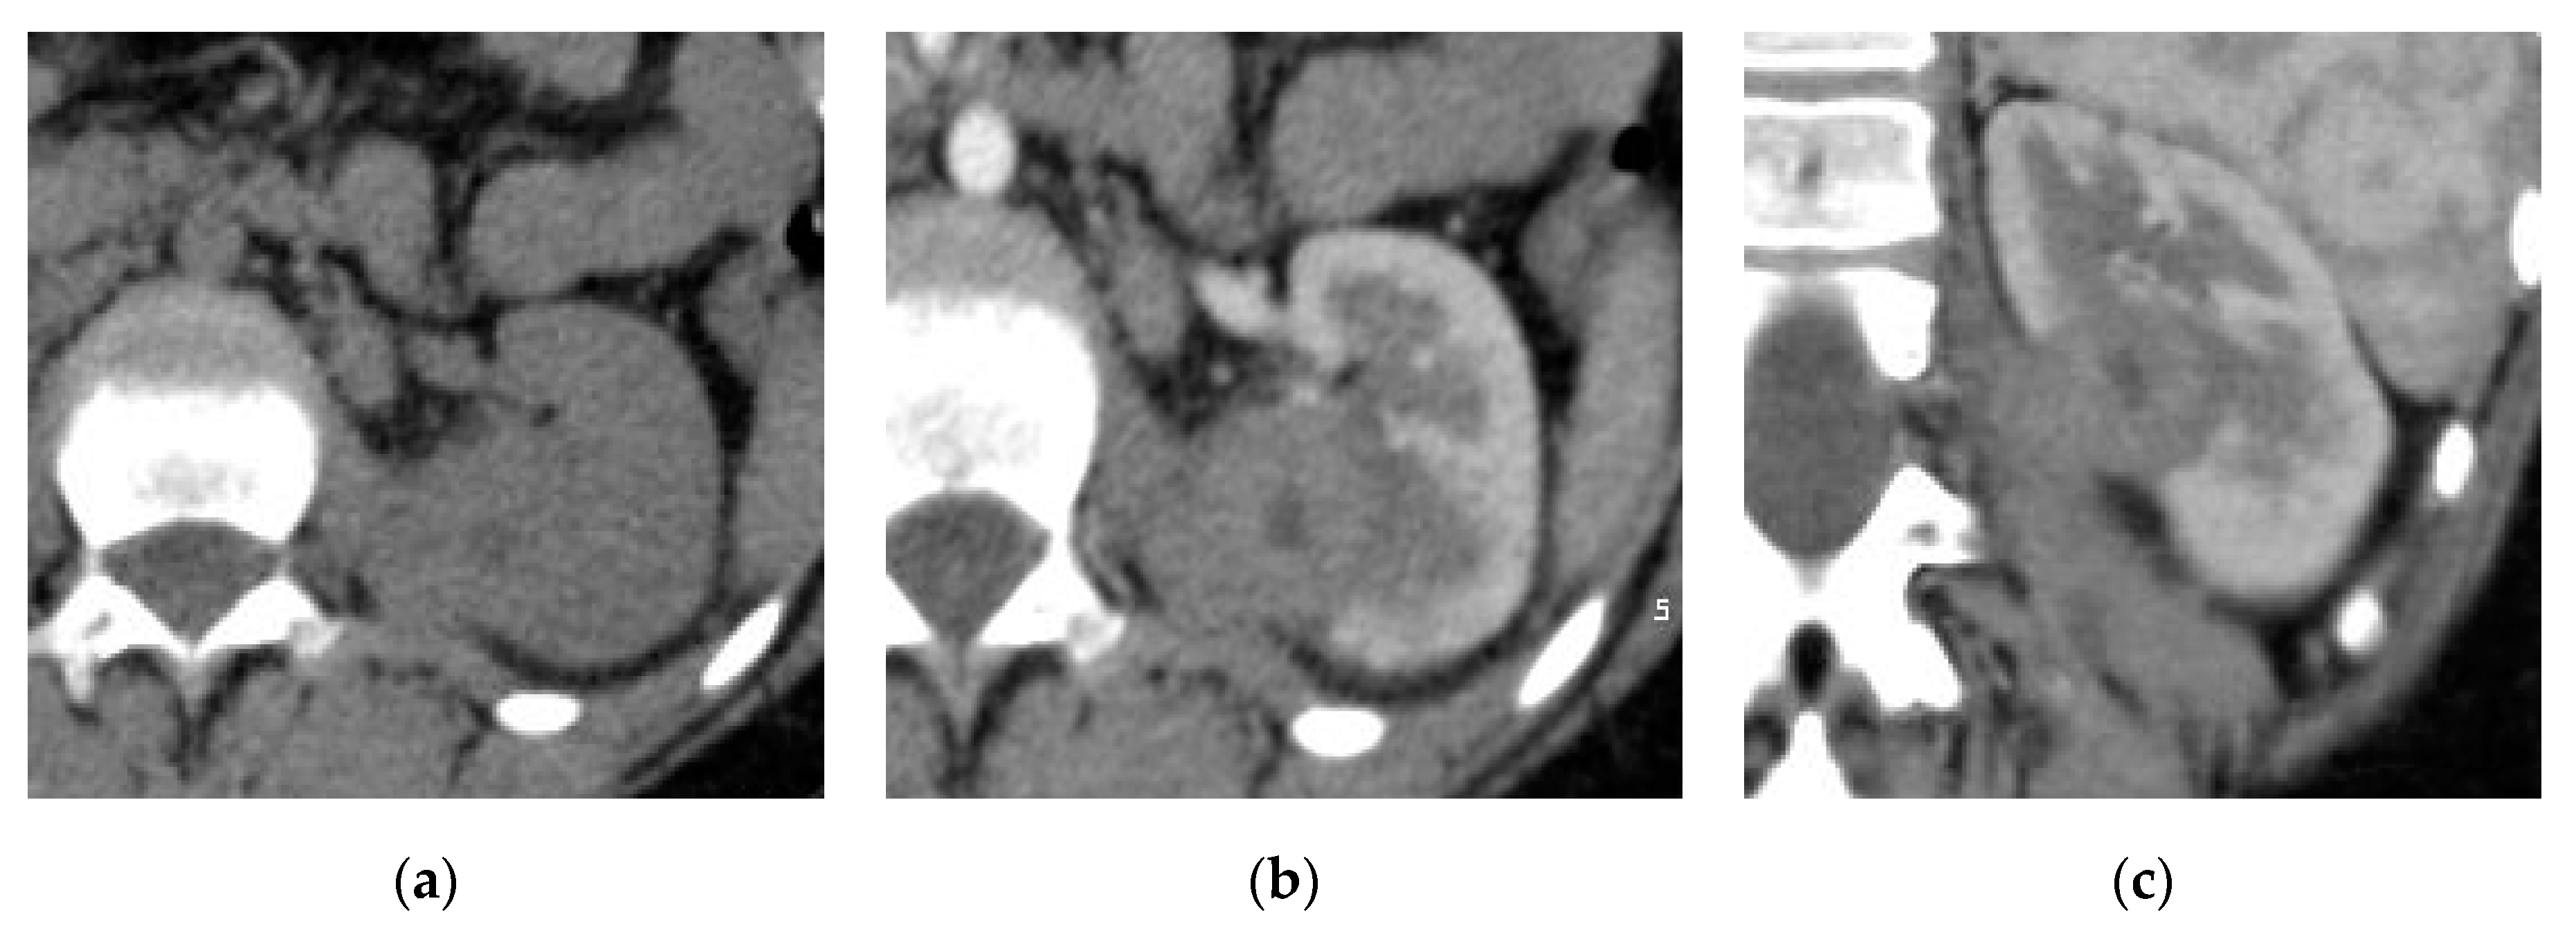

2.1. Acute Pyelonephritis

| Acute pyelonephritis | Wedge shaped hypo-enhancing areas or striated nephrogram pattern. Perinephric fat stranding and thickening of Gerota’s fascia. |